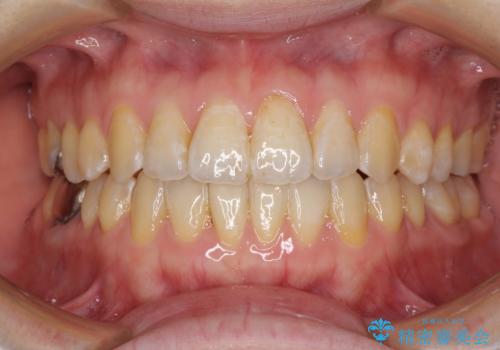

ワイヤーによる全体的ながたつきの矯正治療